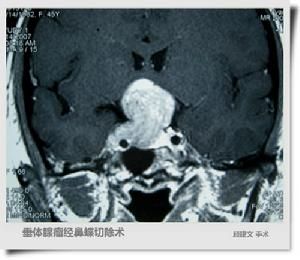

CT圖(4)中西結合、辨證施治。傳承了中醫辯證施治的精髓,將中醫治療不育傳統經驗和現代西醫科學治療方法結合,實現標本兼治,能在短時間內恢復睪丸正常功能,提高雄性激素分泌水平和精液、精子的質量,徹底改善生精內環境。